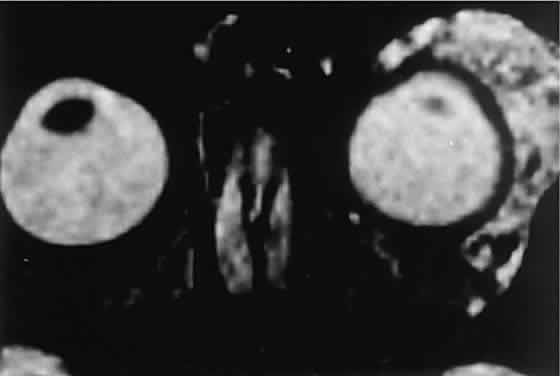

RHABDOMYOSARCOMA Rhabdomyosarcoma is the most common soft-tissue sarcoma in patients younger than 15 years of age and the most common primary orbital malignancy in childhood. These facts should not imply its frequent occurrence. Including all body sites, the annual incidence of childhood rhabdomyosarcoma in the United States is approximately 225 cases.2 The orbit is the site of origin in 5% to 25% of cases.3,4 However, site distribution varies with age. In children 5 to 9 years of age, for example, approximately 40% of primary rhabdomyosarcomas involve the orbit or eyelid.2 Although relatively rare, the tumor has a devastating natural history and demands a high index of suspicion in all cases of pediatric proptosis. Orbital rhabdomyosarcomas are slightly more common in females, with a 0.79 to 1 male-to-female ratio.2 The average age of presentation is 7.8 years, but the tumor may be present at birth and has been reported in patients as old as 78 years.5 A positive family history and associated anomalies have at times been identified, but these are exceptions rather than the rule. Classically, orbital rhabdomyosarcoma presents in an abrupt manner, with rapid progression of proptosis over days to weeks. A somewhat more indolent course does not exclude the diagnosis, however. Vigilance also should be exercised when rapidly expanding eyelid lesions are encountered. Rhabdomyosarcoma may present as ptosis or an eyelid mass rather than with proptosis.4 An eyelid rhabdomyosarcoma can occur as a congenital lesion.6 Within the orbit, rhabdomyosarcoma occurs most often, but not exclusively, in the superior nasal quadrant, with downward and outward displacement of the globe. CT scans show the topography of the orbital mass (Fig. 1A), as well as the possible extension into adjacent bone, paranasal sinuses, or the intracranial cavity. The circumscription that may be noted on CT is relative, because the lesion is not encapsulated and microscopically infiltrates normal tissue. Echography shows internal echoes of low-to-medium amplitude. Because the cellular tumor absorbs acoustic energy, the amplitude of the spikes falls off somewhat through the lesion (see Fig. 1B and C). MRI can help define the tumor's relationship to extraocular muscles (Fig. 2). The clinical diagnosis must be confirmed by biopsy. Because of the risk of seeding the biopsy tract, a transcranial approach should be avoided. If possible, the periosteum should not be violated because it presents a relative barrier to tumor invasion. Depending on its location, the lesion should be approached transconjunctivally or with an eyelid crease incision/transseptal dissection. The surgeon must balance the benefit of complete gross tumor resection with the risks of functional impairment and tumor dissemination that may accompany that effort. Tissue samples should be fixed in formaldehyde solution and glutaraldehyde for light and electron microscopic study. In addition, the value of immunohistochemical differentiation has been established for some time, and the potential uses of molecular genetic studies are rapidly emerging. Consequently, the procurement of fresh or frozen tissue, or both, has been given the highest priority by the Biopathology Discipline within the Intergroup Rhabdomyosarcoma Study Group (IRSG).2 These techniques can facilitate the diagnosis of poorly differentiated tumors, and they may refine diagnostic and prognostic classifications, identify candidate genes, and contribute to potential gene therapies. Since the inception of IRSG-I in 1972, the multicenter collaboration has enrolled the overwhelming majority of patients diagnosed with rhabdomyosarcoma in the United States and has contributed significantly to enhanced patient survival. Patients with orbital tumors had a 96% versus 83% failure-free survival in IRSG-IV compared with those in the IRSG-III.2 As of the year 2000, with the IRSG-V study underway, the overall (all primary sites) 5-year survival of children and adolescents with nonmetastatic and metastatic tumors was approaching 80%. This progress reflects advances in diagnostic imaging and multimodal treatment, including chemotherapy (e.g., agents, combinations, timing), radiation therapy (e.g., doses, fractionation, timing), and surgery (e.g., diagnostic biopsy, local staging, salvage procedures). Therapeutic protocols have evolved over the past 30 years, but they also have not been uniform at any given point in time. Rather, they have been tailored to the patient's level of risk, as determined by multiple prognostic factors (Table 3). The concept of “risk-appropriate therapy”7 recognizes, for example, that a 6-year-old child with an embryonal rhabdomyosarcoma confined to the orbit might do well with a relatively simple chemotherapy protocol, avoiding the late adverse effects of high-dose radiation. Conversely, an 18-year-old patient with an alveolar rhabdomyosarcoma arising in the retroperitoneum, with metastases at presentation, needs aggressive, complex chemotherapy and radiation, and may still do poorly. Prognostic factors considered by the multidisciplinary team include the presence of gross or microscopic residual tumor, and this determination currently is being redefined with molecular techniques that may show residual disease even without microscopic evidence2; whether tumor is confined to the anatomic site of origin or invades surrounding tissues; tumor size, with 5 cm considered a breakpoint; regional lymph node involvement; and distant metastasis. Body site plays a role, and the orbit is relatively favored. The age of the patient at diagnosis is a strong independent predictor of outcome.7 The current pathologic classification for childhood rhabdomyosarcomas by prognosis2 is as follows: